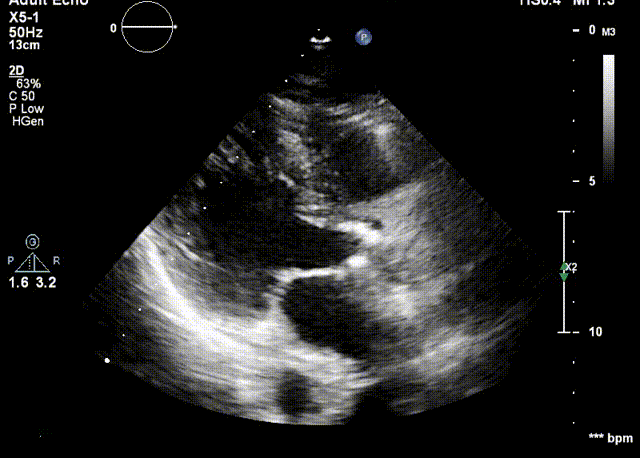

检查结果-术中超声

检查结果-即刻超声

动脉瓣瓣周轻度反流。

经主动脉口收缩期血流最大速度约1.5m/s,最大跨瓣压差约10mmHg。

术后24h心超

● EF 68% 。

● 主动脉瓣未见明显反流。经主动脉瓣口收缩期最大流速约1.9m/s,最大压差约15mmHg,心率约95bpm。

● 二尖瓣轻度反流 。

● 三尖瓣轻度反流,最大反流速度约2.9m/s,估测肺动脉收缩压约44mmHg。

● 经左室流出道收缩期最大流速约1.9 m/s。